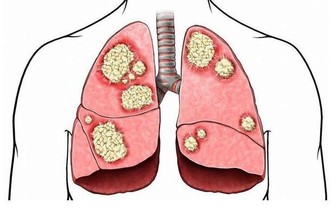

6、戒菸戒酒

吸煙、喝酒的男性比比皆是,對身體的影響不容忽視,香煙和酒可連累全身每一個器官,包括心臟、肺部和肝臟、胃部等,所以戒菸戒酒很有必要。